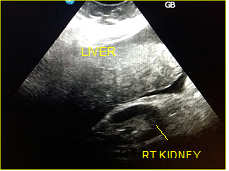

In a 4-years period (from 2016 to 2019) a retrospective study of 887 patients with fatty infiltration of the liver was performed, out of which 608 were males and 272 were females, aged 42 to 69 and 7 obese children (age from 8 to 13 years). All patients were examined in the ultrasound cabinet of our hospital (hospitalized, regular appointments and emergency incidents) and subjected to upper abdominal ultrasound scan, with convex transducer 4C MHz, in three ultrasound imaging planes: transverse, oblique and sagittal planes.5−7 In order to better depict the liver, especially in obese patients or those with excessive intestinal gas, the patients were asked to inhale deeply and hold their breath for the duration of the ultrasonographic examination for a few seconds at a time, so that the liver could be visible in its entirety. The ultrasound examination revealed the echogenicity of the parenchyma of the liver and was compared with the parenchyma of the right kidney, the spleen and the pancreas (Figure 1−3). Τhere is always the risk of missing a diagnosis of mild hepatic steatosis on ultrasound if there is concurrent chronic renal disease, which increases the echogenicity of the kidneys (Figure 4), if there is any doubt that the patient might have a chronic renal disease, comparison of the liver to the left kidney and the spleen may be useful.8

Figure 4 Chronic renal diseases, which increase the echogenicity of the kidneys.

The fatty infiltration of the liver is shown on ultrasound with significantly increased echogenicity "bright liver", in comparison with the right kidney cortex (Figure 1). Normally, the liver and the renal cortex have similar echogenicity, relative to the parenchyma of the pancreas and the spleen. The maximum diameter of the liver in the midclavicular line (MCL) was increased, right lobe>15 cm (Figure 5). Also significant features are the absence of mass effect on intrahepatic vasculature (Figure 6) as well as the poor visualization of the deep parts of the liver (Figure 7), due to decreased permeability of the acoustic beam. A focal or diffuse morphology has been shown to increase the echogenicity of the fatty liver. Differential diagnosis is caused by focal fat infiltration (Figure 8), which has a geographic distribution. In this case, hypoechoic areas correspond to normal hepatic parenchyma on fatty infiltration sites, whereas, normal parenchyma islets can easily be identified due to their typical positions, in front of the right branch of the portal vein, its division, around the area of the gallbladder and the caudate lobe.9−13